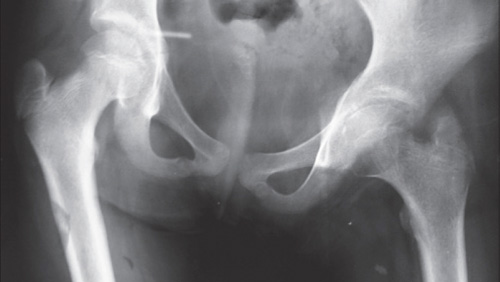

Остеоартрит (ОА) тазобедренного сустава или коксартроз является болезненным заболеванием, которое может влиять на один или несколько суставов. Он характеризуется потерей хряща, часто сочетающимся с воспалением и изменением костей, ближайших к суставу. Это приводит к боли, жесткости и затруднению перемещения сустава. ОА может быть вызван рядом факторов, которые включают избыточный вес, повреждение суставов и старение. Любой сустав может быть подвержен коксартрозу, но чаще всего это происходит в руках, коленях, бедрах и позвоночнике. В этой статье мы рассмотрим эффективное лечение коксартроза.